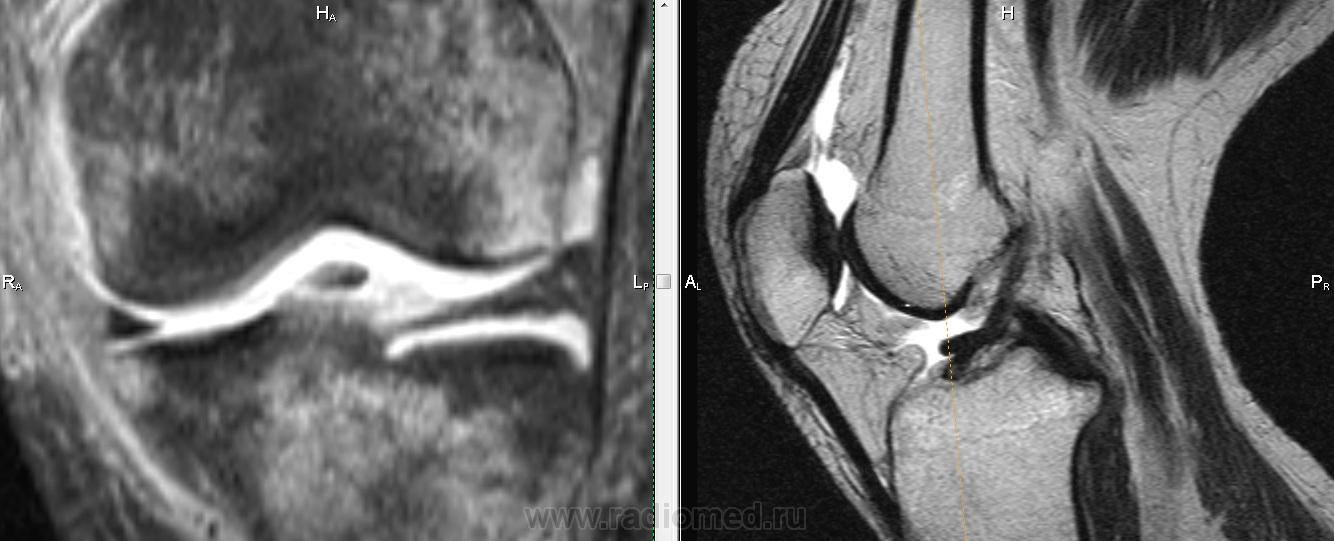

Падение с велосипеда. Вперед выступает фрагмент ПКС?

Не очень понятно, Михаил Александрович.Как-будто бы симптом "двойной  крестообразной связки", но не совсем похоже: при  этом  связка как-бы дугообразно идет.И мениски визуально вроде бы целы.Не может это быть фрагментом  переднего рога мениска?

Трудно сказать, на фрагмен мениска более похоже. Да и ПКС не отечная и внутренний мениск какой-то дефицитный. Если вопрос о цесостности ПКС обычно косая проекция выручает.

Думаю , тут фрагмент   переднего рога и части тела  латерального мениска ,  он(фрагмент) совсем  оторвался и уплыл кпереди .